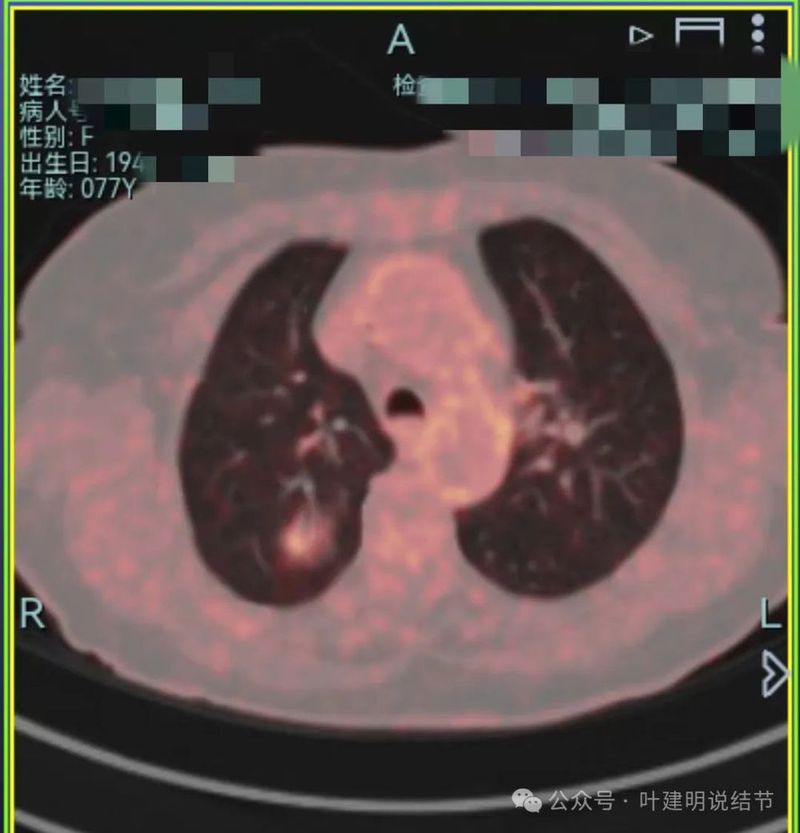

其他检查:

就诊医院给她做了PET-CT,报告示右上叶后段FDG代谢增高灶,考虑肺原发低代谢恶性肿瘤可能。

上图示代谢有增高。

上图显示冠状位与矢状位形态。其实已经不重要,本来就已经基本可断定是恶性的了。